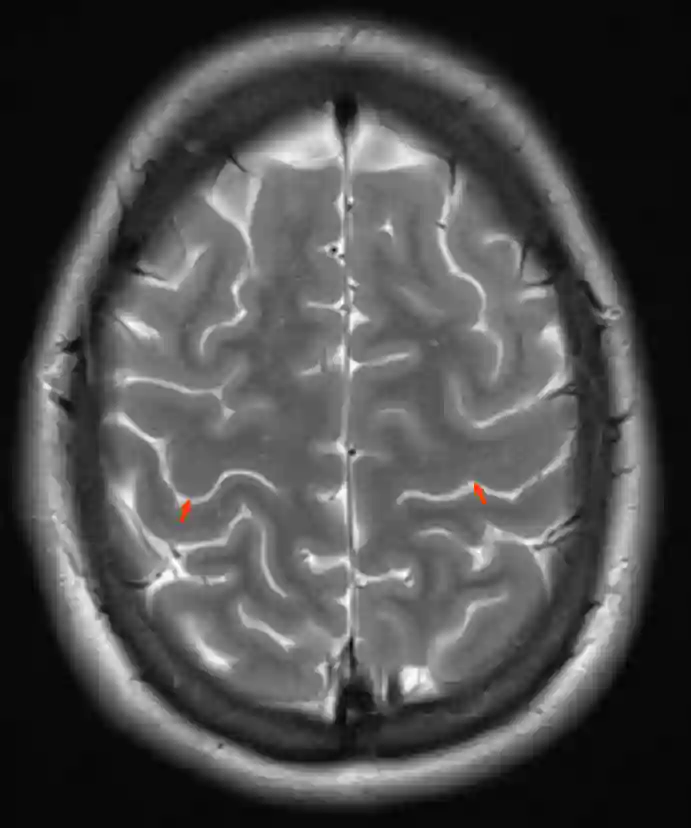

Sulcus centralis MRI

Darstellung des Sulcus centralis (roter Pfeil) in einem T2 gewichtetem axialen MRI Bild.